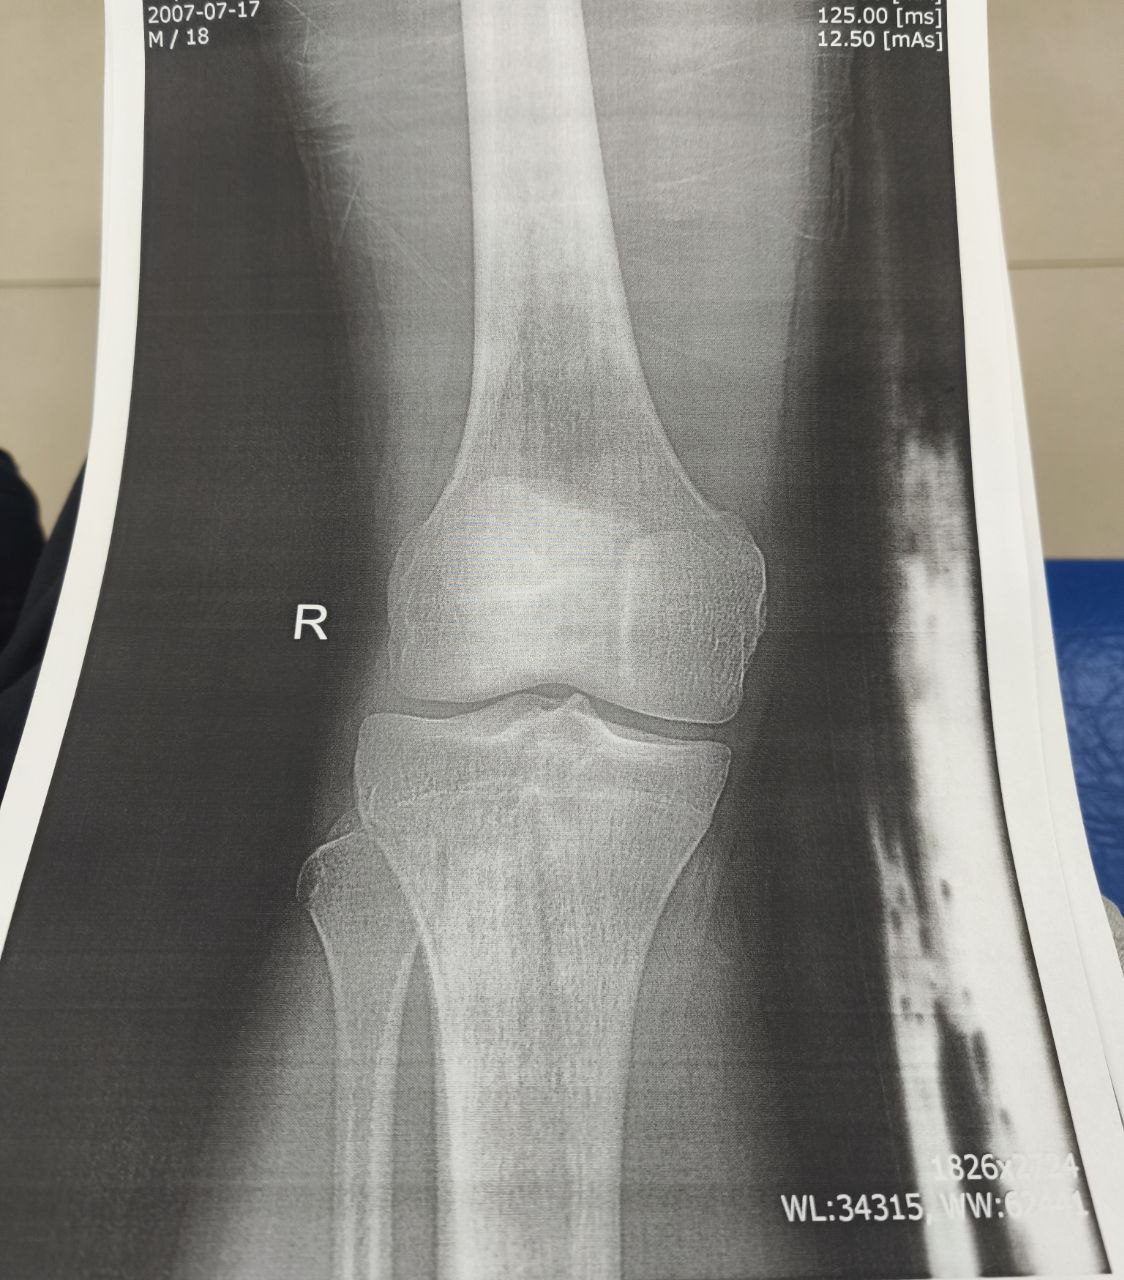

Помогите расшифровать снимок